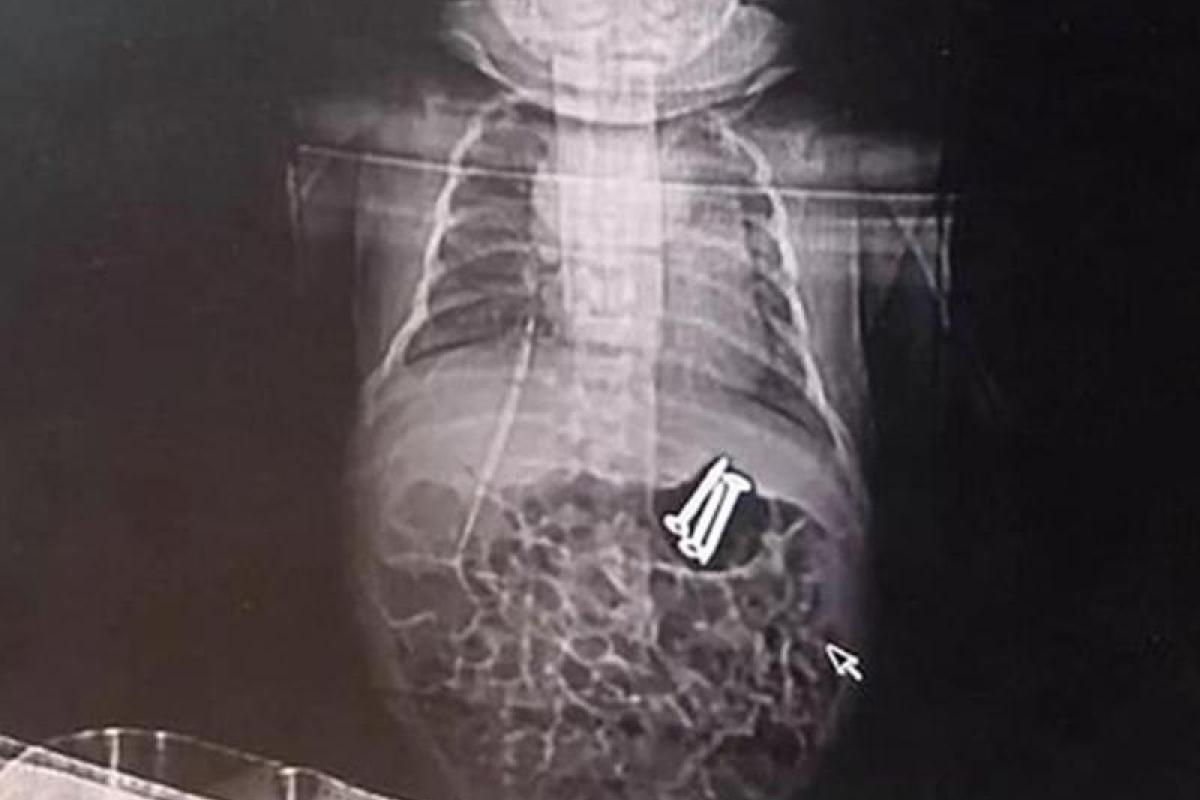

Инцидент произошел в городе Чжэнчжоу. Китаянка оставила дома двух своих детей, так как решила, что старший брат сможет присмотреть за месячным младенцем. Однако когда вернулась домой, то обнаружила, что у малыша изо рта идет пена. Женщина немедленно отнесла его в больницу, где ребенку сделали рентген и обнаружили в желудке три гвоздя, передает Час Пик со ссылкой на зарубежные СМИ.